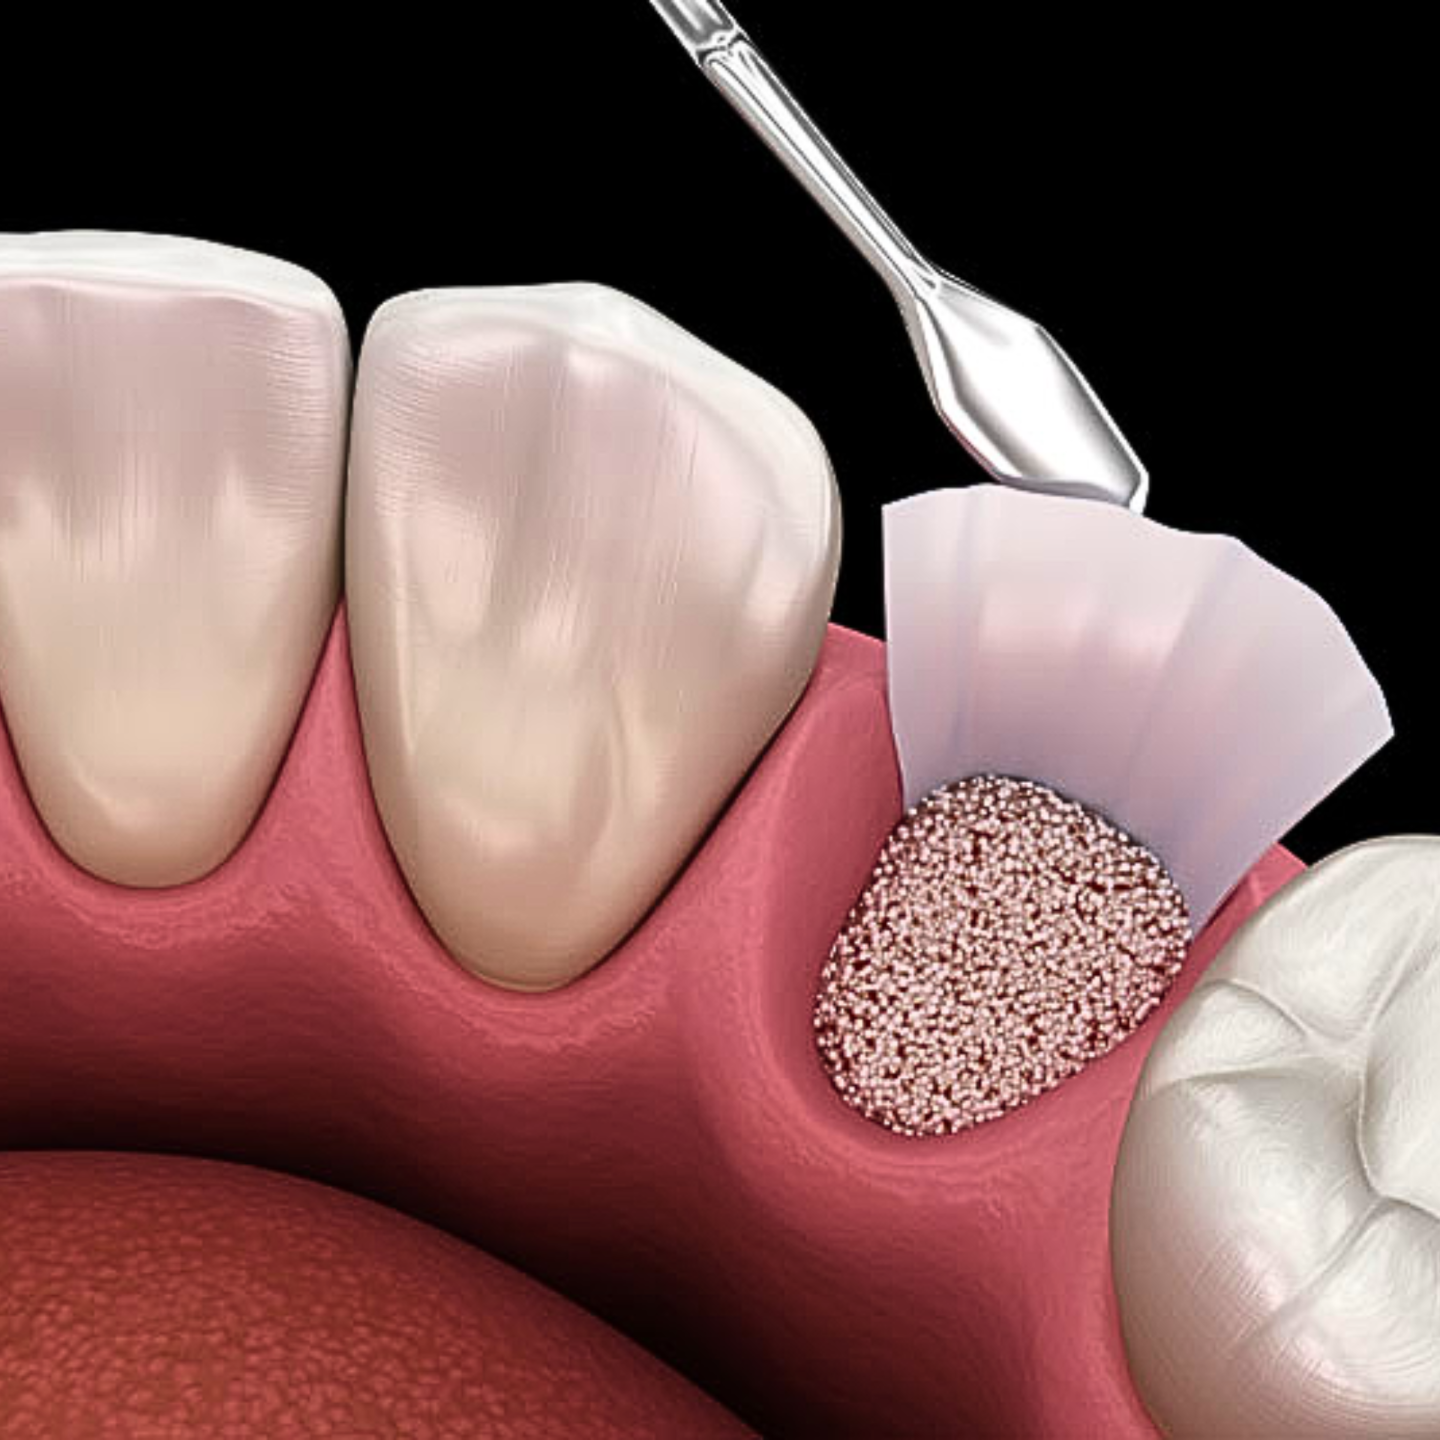

Socket Preservation & Bone Grafting Protocols

Step-by-step guidance on graft materials, membranes, and techniques to preserve ridge integrity and prep for implants.

- Step-by-Step Grafting Mastery – How to select and apply different grafting materials (autografts, allografts, xenografts) for predictable healing.

- Membrane Selection & Placement – When, how, and why to use membranes for ridge preservation and graft success.

- Biologics and Soft Tissue Tips – Discover why soft tissue management can transform your long-term results.